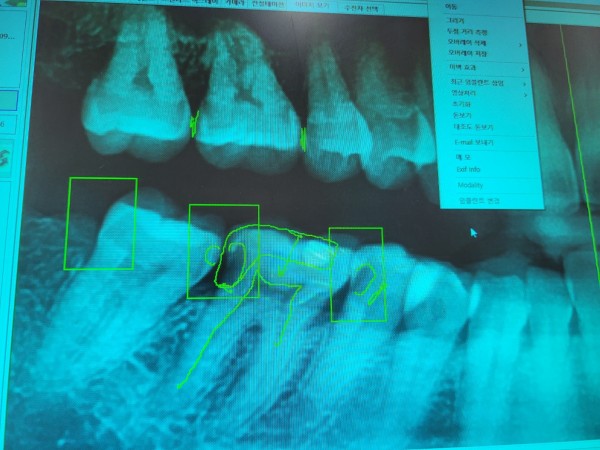

타 병원에서 엑스레이상에 체크된 아래 어금니 세개와

윗 이 한개 치료가 필요하다고 들었는데요..

아래 어금니 세개와 윗 이 한개 이렇게 4개 치아 모두 치료를 받아야 하는 상황인건지 궁금하구요.

되도록이면 신경치료는 받지 않고 싶은데..

치료를 할 경우 아래쪽 끝에서 두번째 어금니는 엑스레이상으로 봤을때 신경치료가 꼭 필요한 상황인지 궁금합니다.

비용은 어느정도 생각해야 하는지도 알고 싶습니다. 감사합니다!